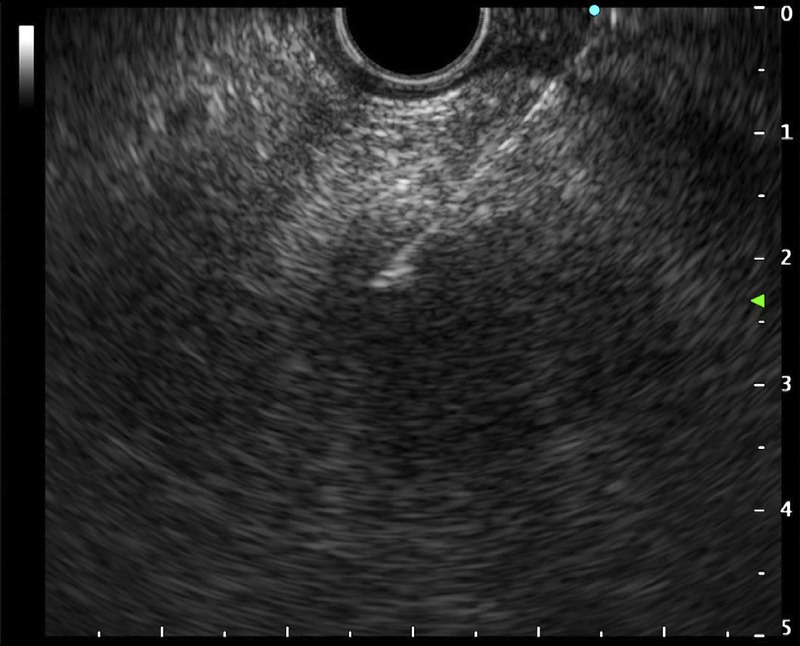

Abstract Image